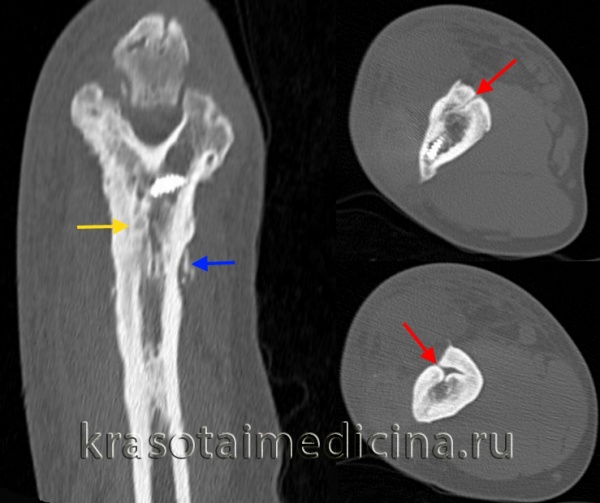

КТ локтевого сустава. Утолщение кортикального слоя плечевой кости за счет гиперостоза/остеосклероза (желтая стрелка), периостальные наложения (синяя стрелка), свищевые ходы (красная стрелка).